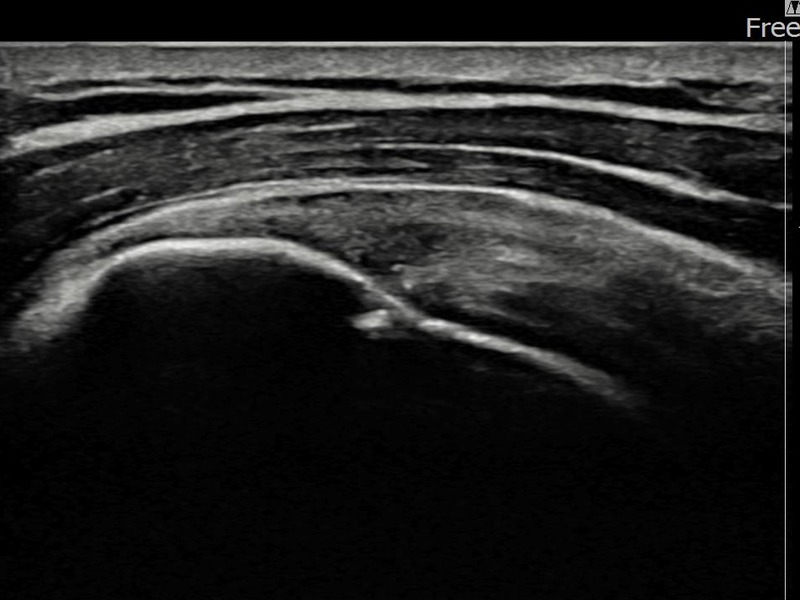

김ㅇㅇ님 · 좌측 극상근건 광범위 부분파열

좌측 어깨 광범위 파열로 수술을 권유받았으나 비수술 치료를 원해 내원하셨습니다. 초음파 검사에서 극상근건 전층에 걸친 광범위 부분파열이 확인되었으며, 어깨인대 축소봉합술 후 구조적 안정화와 기능 회복이 이루어졌습니다.